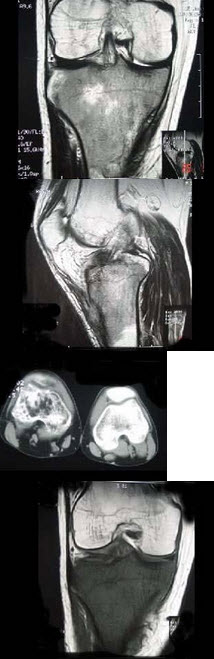

女,41岁,慢性肾功能不全,结合图像,最可能的诊断是( )

A:白血病

B:甲状旁腺功能亢进

C:地中海贫血

D:镰状细胞贫血

E:骨关节结核